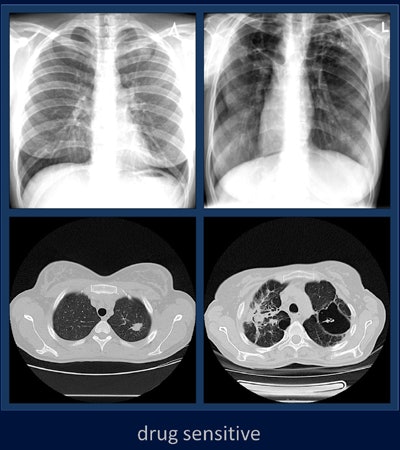

Tuberculosis remains a serious public health problem in many countries due to the rising incidence of drug-resistant cases. To distinguish drug-sensitive from drug-resistant cases, this study looked at the use of features on CT and x-ray images to predict drug resistance in tuberculosis patients.

The chest radiographs were acquired using a commercially available computed radiography (CR) system (Point-of-Care CR 260 system, Carestream Health) with 2,248 x 2,248-pixel resolution, while CT scans were acquired on a 16-detector-row scanner (LightSpeed Pro 16, GE Healthcare) at a slice thickness of 2.5 mm.

Lung regions were segmented semiautomatically on CT and manually on radiographic images, with final inspections performed by a radiologist, Kovalev and colleagues wrote.